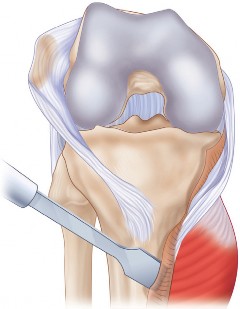

استبدال مفصل الركبة التقوسي هو إجراء جراحي ناجح يخفف الألم ويعيد وظيفة الركبة المشوهة. يتضمن تصحيح الانحراف المحوري للركبة وإعادة توازن الأنسجة الرخوة لتحقيق استقرار طويل الأمد، ويُعد الحل الأمثل لمرضى خشونة الركبة المتقدمة.

الخلاصة الطبية السريعة: تُعد جراحة استبدال مفصل الركبة التقوسي إجراءً جراحيًا رائدًا وناجحًا للغاية، مصممًا خصيصًا لتخفيف الآلام المزمنة واستعادة الوظيفة الطبيعية للركبة التي تعاني من تشوه تقوسي متقدم (خشونة الركبة التقوسية). يتضمن هذا الإجراء الدقيق تصحيح الانحراف المحوري للركبة وإعادة توازن الأنسجة الرخوة المحيطة بدقة متناهية، مما يضمن استقرارًا طويل الأمد للمفصل الاصطناعي. يُقدم الأستاذ الدكتور محمد هطيف، بخبرته التي تتجاوز 20 عامًا كأستاذ لجراحة العظام والمفاصل في جامعة صنعاء، هذا الحل الأمثل لمرضى خشونة الركبة المتقدمة، مستخدمًا أحدث التقنيات الجراحية لضمان أفضل النتائج.

هذه الجراحة ليست مجرد استبدال للمفصل التالف، بل هي عملية تصحيحية شاملة تهدف إلى إعادة المحاذاة الطبيعية للركبة والتخلص من الانحراف التقوسي الذي يسبب الألم ويُسرّع من تدهور المفصل. بفضل الخبرة الواسعة للأستاذ الدكتور محمد هطيف التي تمتد لأكثر من عقدين من الزمن كأستاذ جامعي وجراح عظام متخصص، وباستخدامه لأحدث التقنيات الجراحية مثل الجراحة المجهرية وتنظير المفصل بتقنية 4K وزراعة المفاصل المتقدمة، يتمكن مرضى خشونة الركبة التقوسية في صنعاء من استعادة حركتهم الطبيعية والعيش بلا ألم.

يُعد الانحراف التقوسي مشكلة شائعة وقد يكون خلقيًا (موجودًا منذ الولادة)، ولكنه غالبًا ما يتطور بمرور الوقت نتيجة لخشونة الركبة المتقدمة، حيث يؤدي التآكل غير المتساوي للغضروف إلى تفاقم التشوه. تصحيح هذا الانحراف هو جوهر جراحة استبدال مفصل الركبة التقوسي، وهو ما يتقنه الأستاذ الدكتور محمد هطيف لضمان استقرار المفصل وطول عمره.